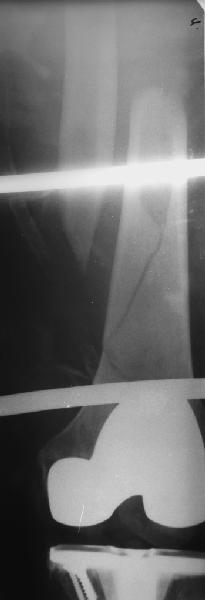

В приложении - недавний перипротезный перелом.

Методичка по закрытому интрамедулярному остеосинтезу при дистальных переломах бедра тут.